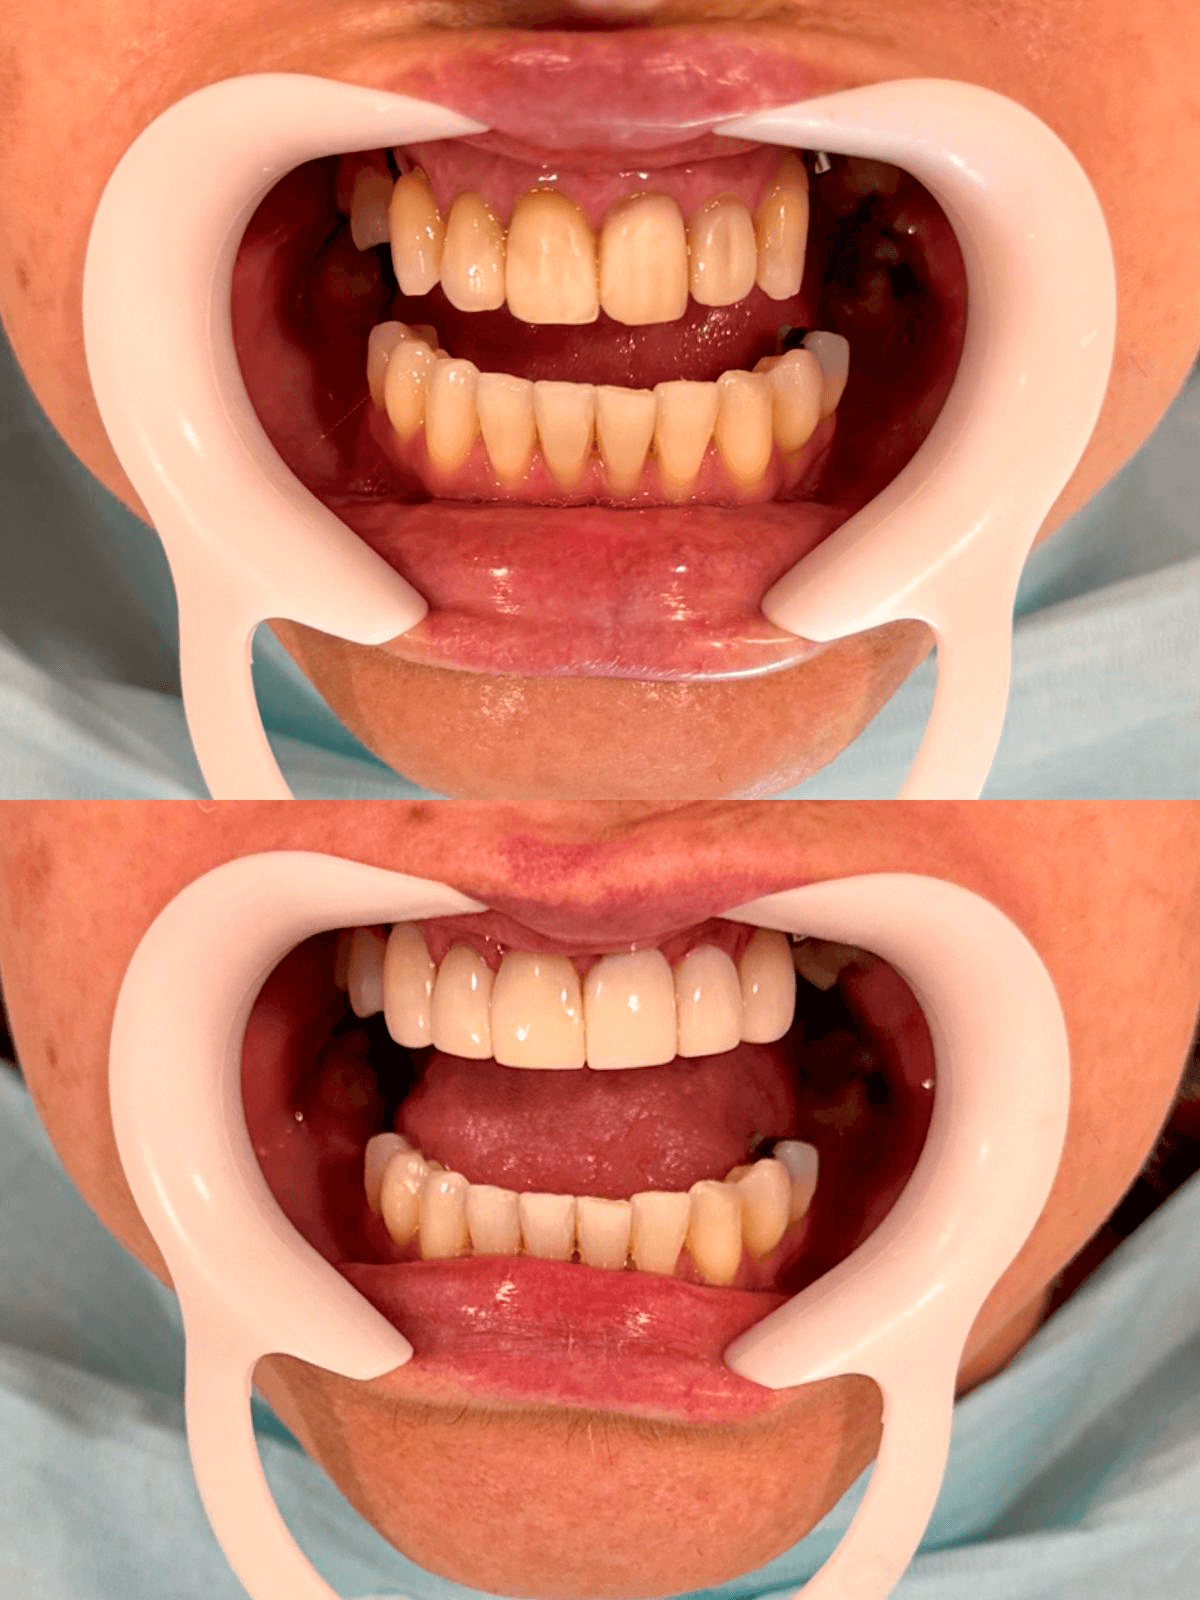

Próteses dentais

O caminho para um sorriso completo e confiante, restaurando sua estética e funcionalidade.

Implante Dentário

A solução permanente e natural para recuperar seus dentes perdidos e sorrir sem preocupações.